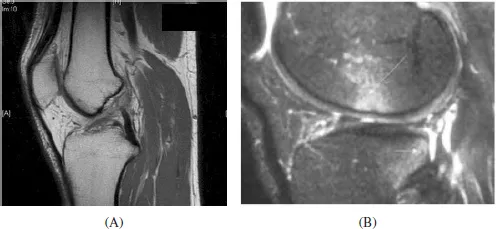

image

Fig. 1. Sagital view of cadaver knee showing anteromedial and posterolateral bundle of ACL. ACL runs from medial aspect of lateral femoral condyle to tibial spine.

Radiographic evaluation of a patient with a suspected ACL injury includes plain radiographs of the affected knee to rule out fracture in the acute setting. Associated injuries that may be identified on plain imaging include a Segond fracture10 (lateral capsular avulsion) and tibial eminence avulsion fractures in skeletally immature patients. Additionally, the presence of open physes is of particular importance as this can impact the surgical treatment approach. MRI is not required for the diagnosis of ACL injury, but it is useful for assessing for associated injuries to the meniscus, other ligaments, the articular surface and for the presence of subchondral bone marrow edema lesions and fractures. The characteristic edema pattern seen on MRI with bone marrow lesions present within the posterolateral tibial plateau and the central lateral femoral condyle correspond to the pivot-shift type translational event that occurs during injury (Figure 2). In the coronal and sagital MRI images, disruptions in the normal black ACL fibers signify ACL injury.

Fig. 2. (A) T1 weighted sagittal MRI showing ruptured ACL. (B) T2 weighted sagittal MRI showing characteristic bone edema seen after ACL tear.